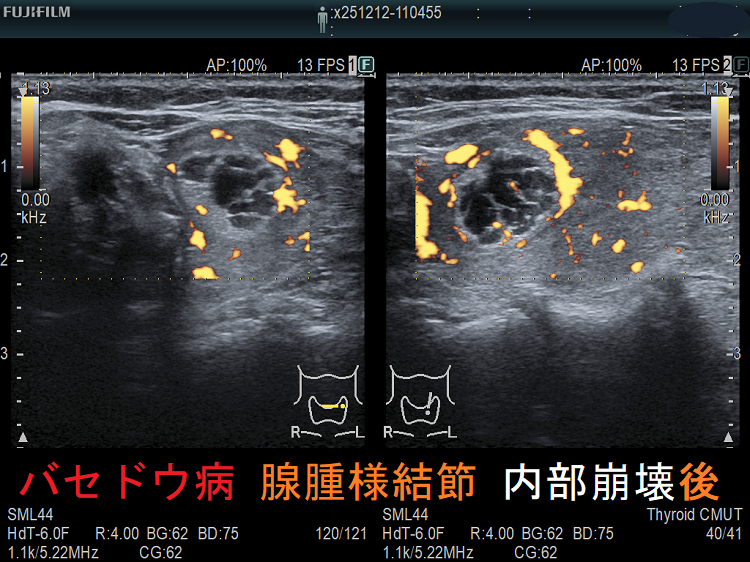

穿刺細胞診後内部融解

ケース①

ケース②